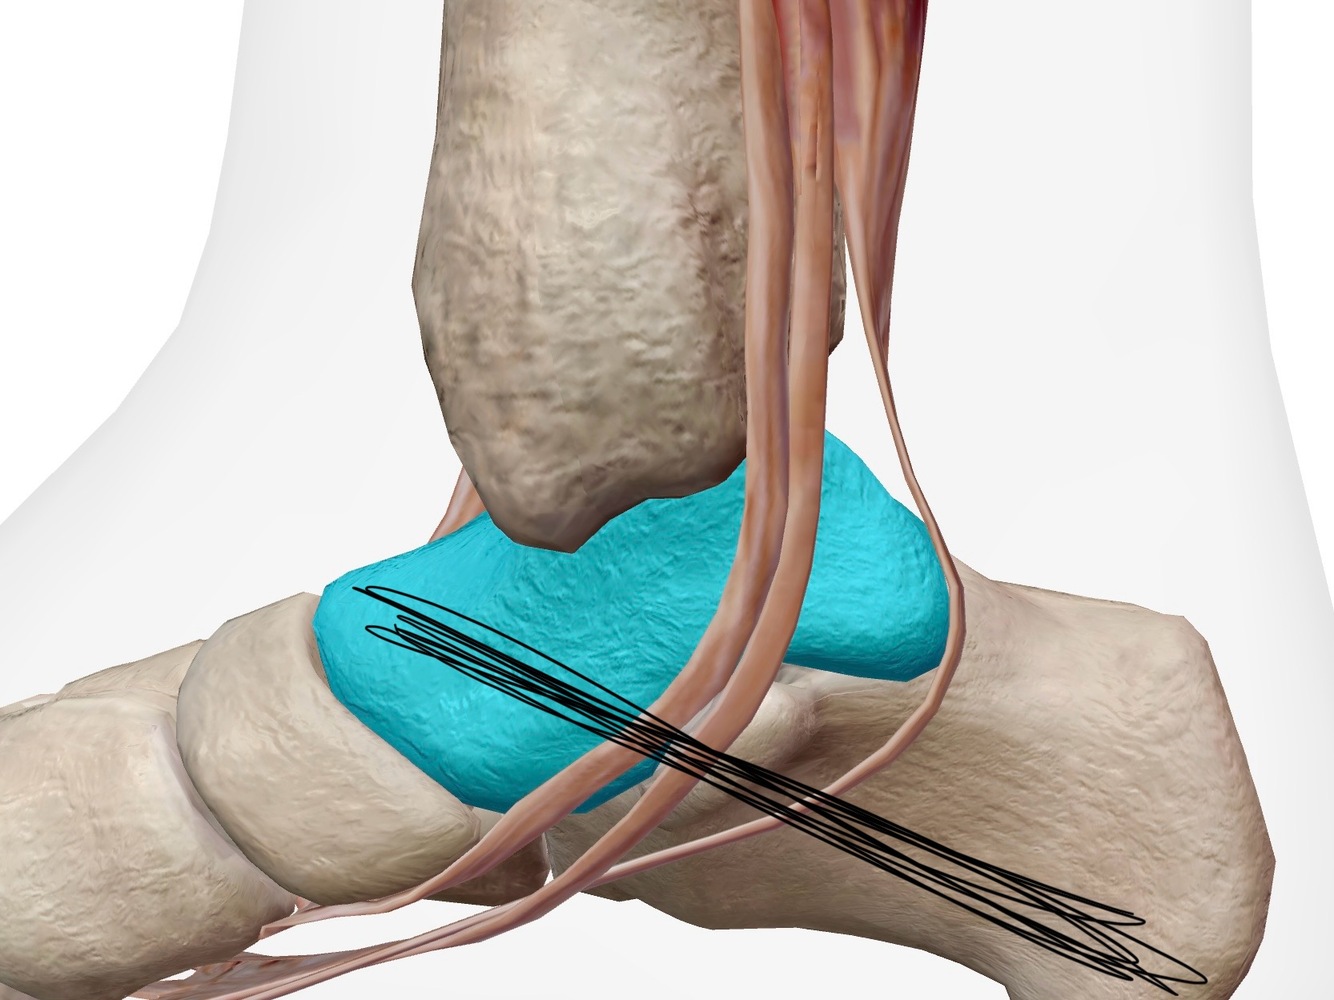

Q

Identifier les structures sur cette image.

Indice: On y voit les os suivants : Tibia, talus et calcanéus

A